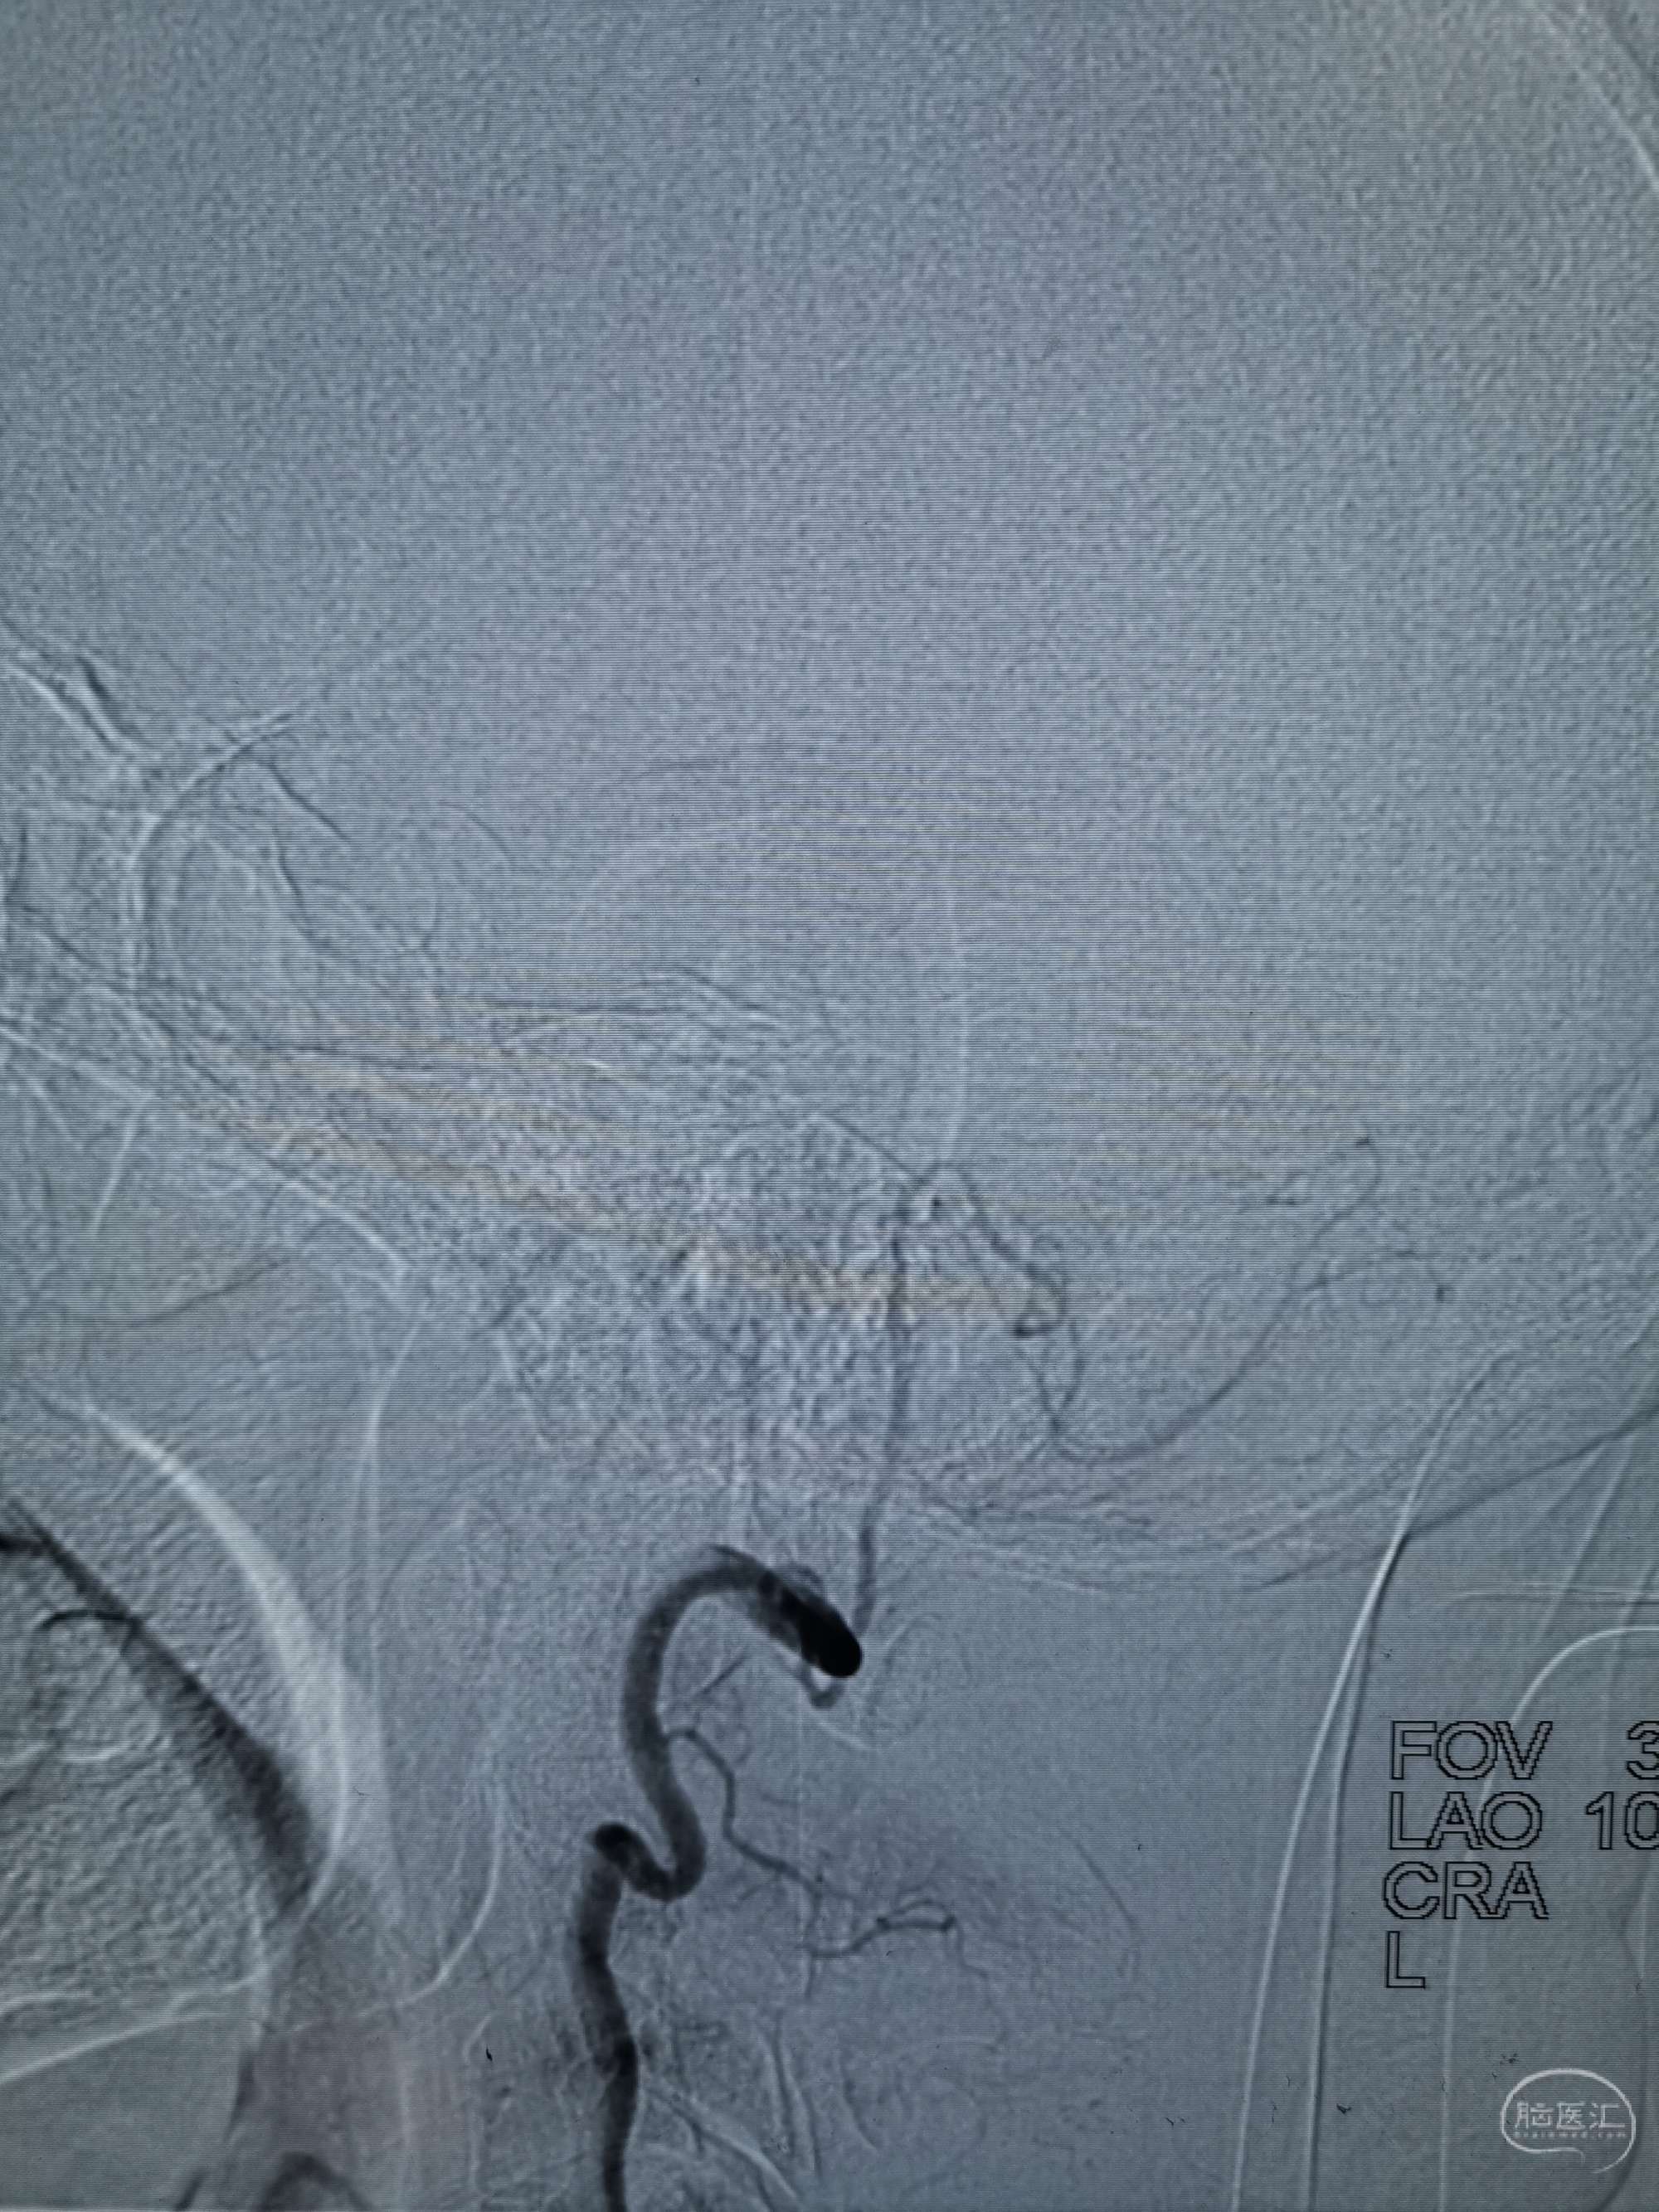

术前再次造影评估

右侧椎动脉穿支供血及左侧PICA供血较入院时略有改善,但改善不明显。故按计划行左侧椎动脉再通术